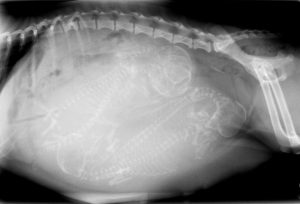

At Animal House Veterinary Clinic in Franklin, NC, we are proud to be on the cutting edge of medical technology. Radiology is a technique and diagnostic tool that we use to look inside the body in an entirely non-invasive way. Our digital X-rays allow us to create images of all the body’s organs.

Our use of radiology gives us a view of the internal organs in your pet’s body that we otherwise could not see. It is a valuable diagnostic tool that helps veterinarians detect and prevent illness.